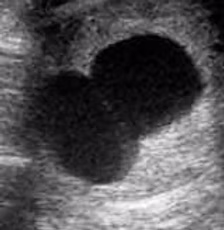

16 Tagen nach der künstlichen Besamung Ihrer Stute ist es möglich eine aussagekräftige Trächtigkeitsuntersuchung mittels Ultraschall durchzuführen. Hierbei ist es besonders wichtig eine Zwillingsträchtigkeit auszuschließen und den Besitzer über die weitreichenden Risiken aufzuklären. Dennoch ist es möglich, beim Vorliegen von zwei Fruchtanlagen eben nur einen gesunden Embryo heranwachsen zu lassen, um sowohl Stute, als auch Fohlen mit möglichst wenig Risiken auszusetzen. Die regelmäßige Untersuchung des Embryos ist bis zum dritten Trächtigkeitsmonat transrektal und später auch transabdominal durchführbar.